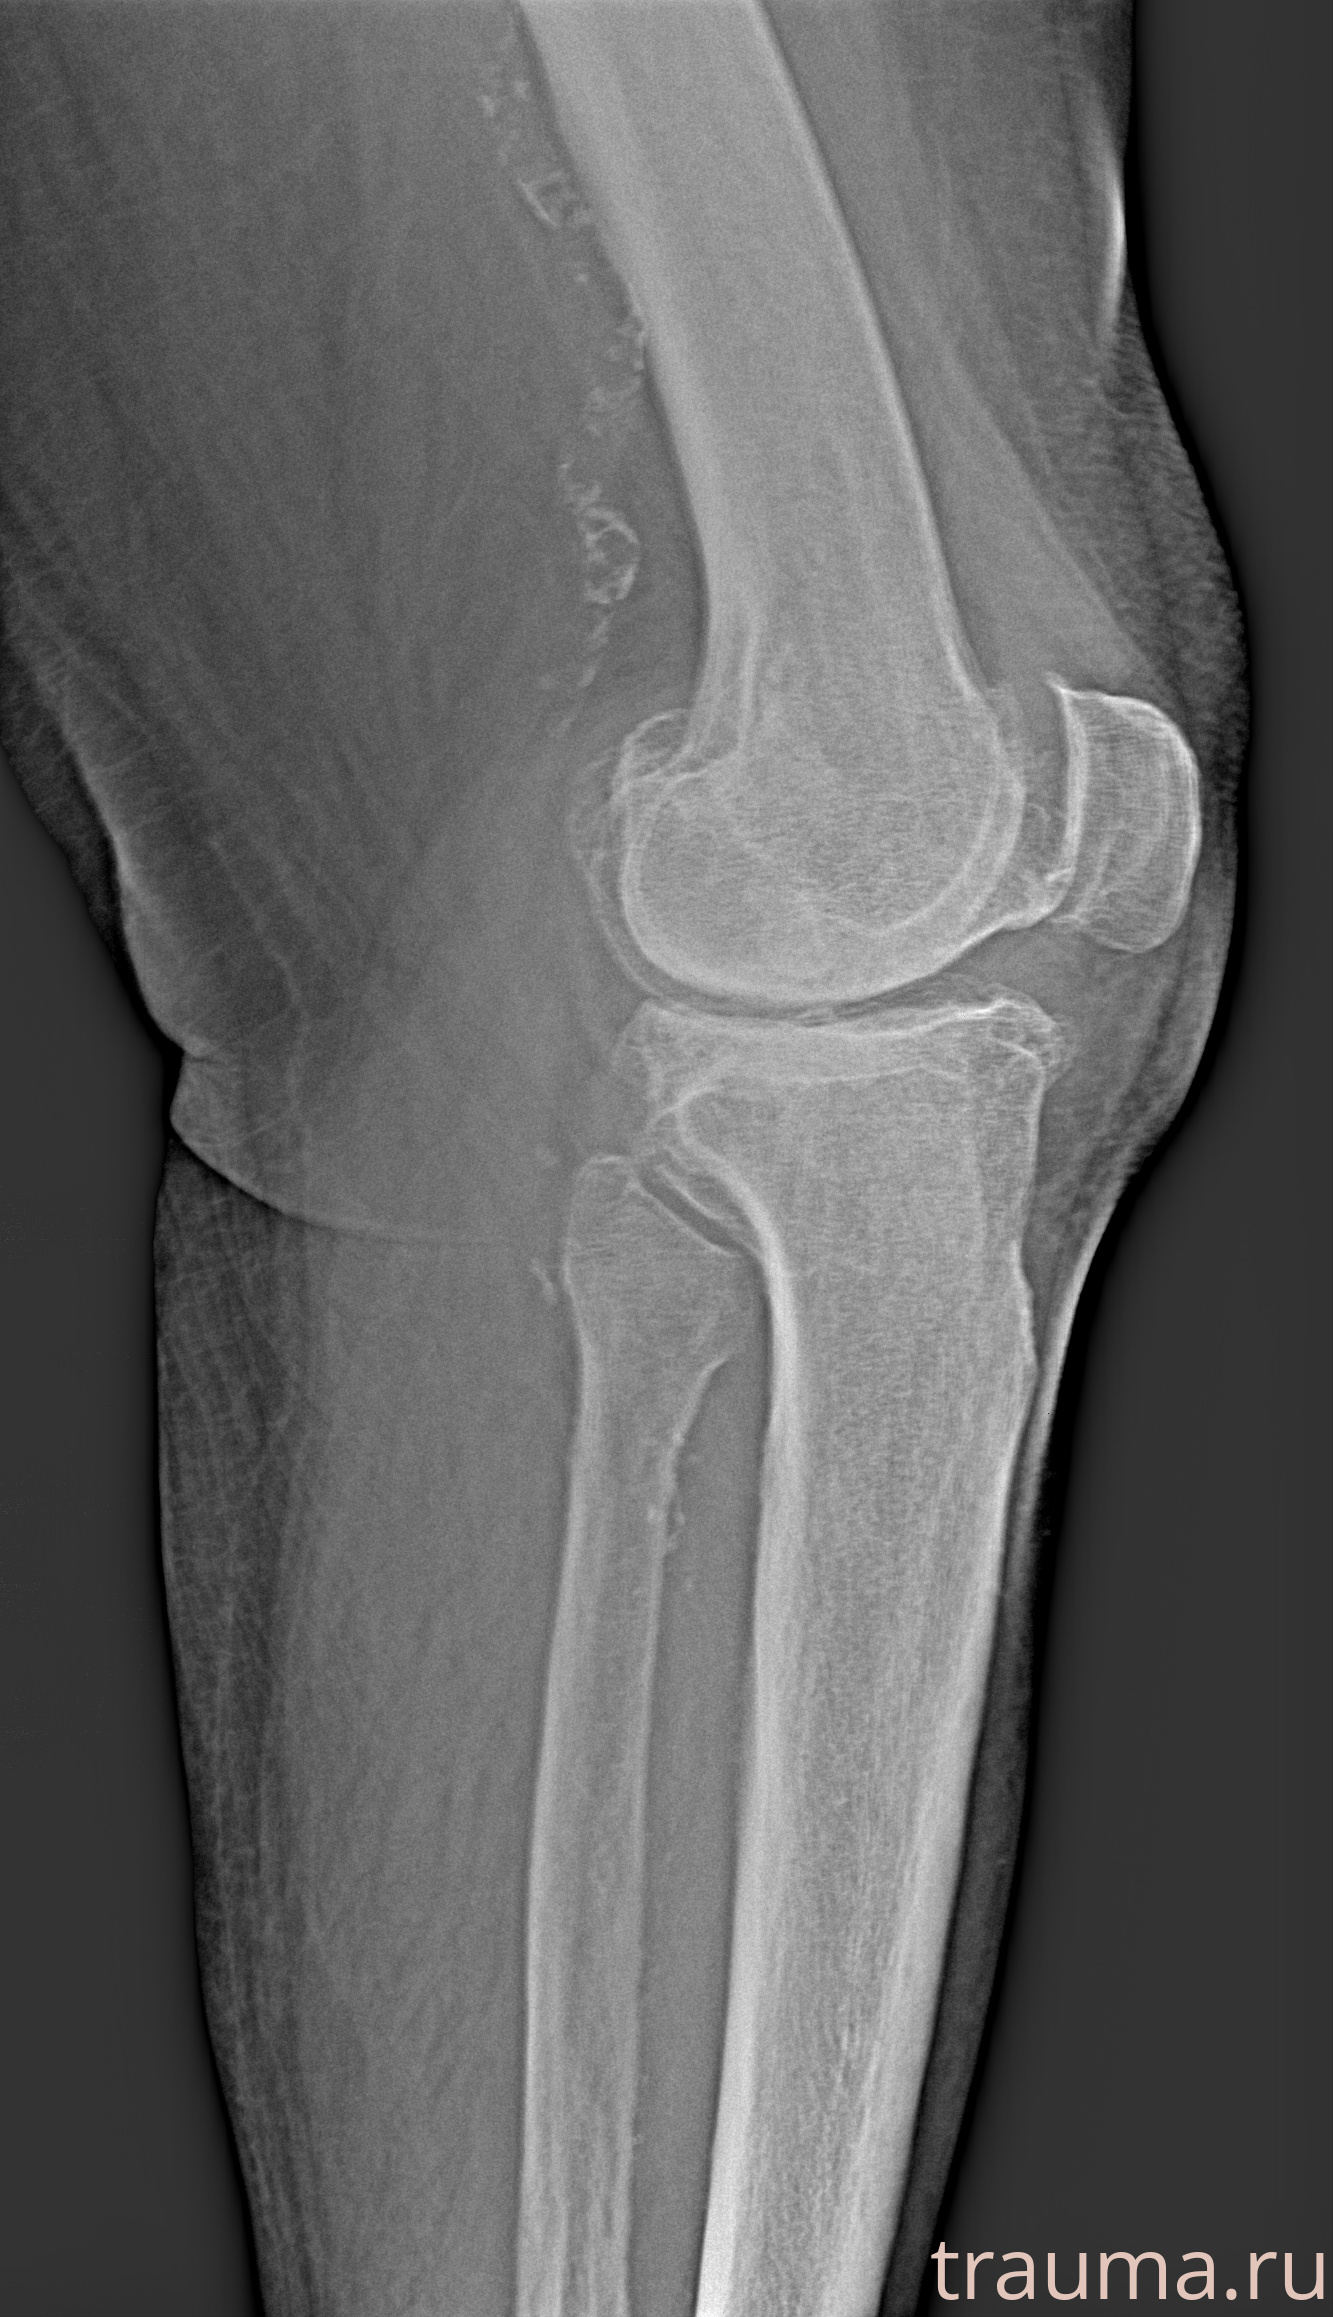

Рентгенограммы

Рентген на дому: по вашему адресу приезжает врач-рентгенолог, травматолог-ортопед с мобильным рентгеновским аппаратом, проводит диагностику травмы или заболевания, делает необходимые рентгенограммы, дает рекомендации по дальнейшему лечению. Получить качественные снимки в домашних условиях возможно благодаря уникальной методике, разработанной МосРентген Центром для института  Склифосовского